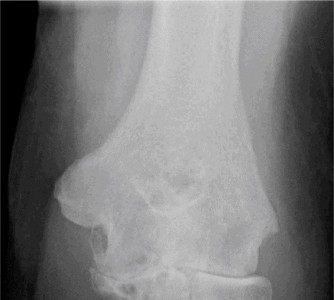

Examination reveals deformity about the elbow with no open lesions or skin tenting. He has a palpable radial and ulnar pulse and is neurologically intact. His images are shown (Figs. 2–85 to 2–88).

Figure 2–85

Figure 2–86

Figure 2–87

Figure 2–88

What is the diagnosis and direction of displacement?

The correct answer is (B). This is the most common type of elbow dislocation, and often does not cause any osseous injury. Posterolateral and posteromedial dislocation account for approximately 90% of dislocations. Adequate pre- and postreduction films are necessary to evaluate for fracture, which would change the classification to a complex injury.